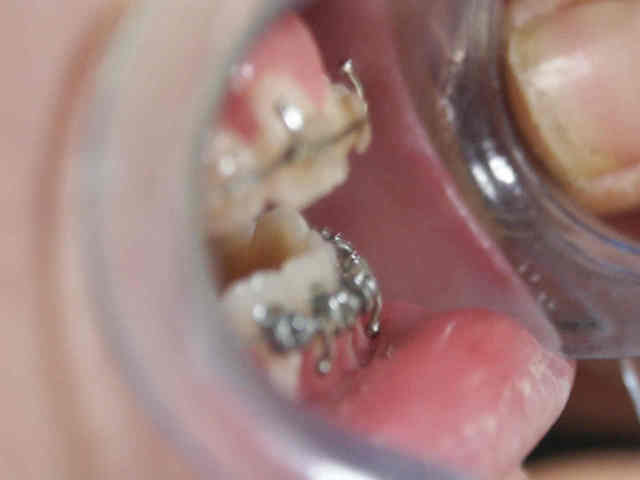

En effet je utilise plutot l'ecran buccal " oral screen " et je n'ai pas dit ecran lingual.il est vendu chez rmo, et j'utilise l'ecran simple dur actuellement je n'ai pas de photo mais j'en fairrai c'est promis. Quant a la langue je prefere la methode active et inter active. C'est a dire l'enfant doit apprendre a gerrer cette langue " mal eduquee " pun eln ou la langue se remet en place tant que l'eln est en place, et apres??? Je travaille avec la methode evolutive:

1- apprendre a connaitre la bonne position de la langue sans rien ou a l'aide des pastilles en choco "smarties" ou des elastiques inter maxillaires a coincer entre la langue et le palais

2- Quand la posture est plus ou moins ressentie, reconnue et controlee par le patient je commence la fonction c'est a dire la deglutition

3- pour les cas tres dificils j'utilise le eln ou j'envoie chez un kine pour amener l'enfant a un stade ou je peux continuer sans perdre trop mon temps.

Concretement c'est ce que je fais. Mais je mets la responsabilite sur le dos de tout le monde et surtout la maman.